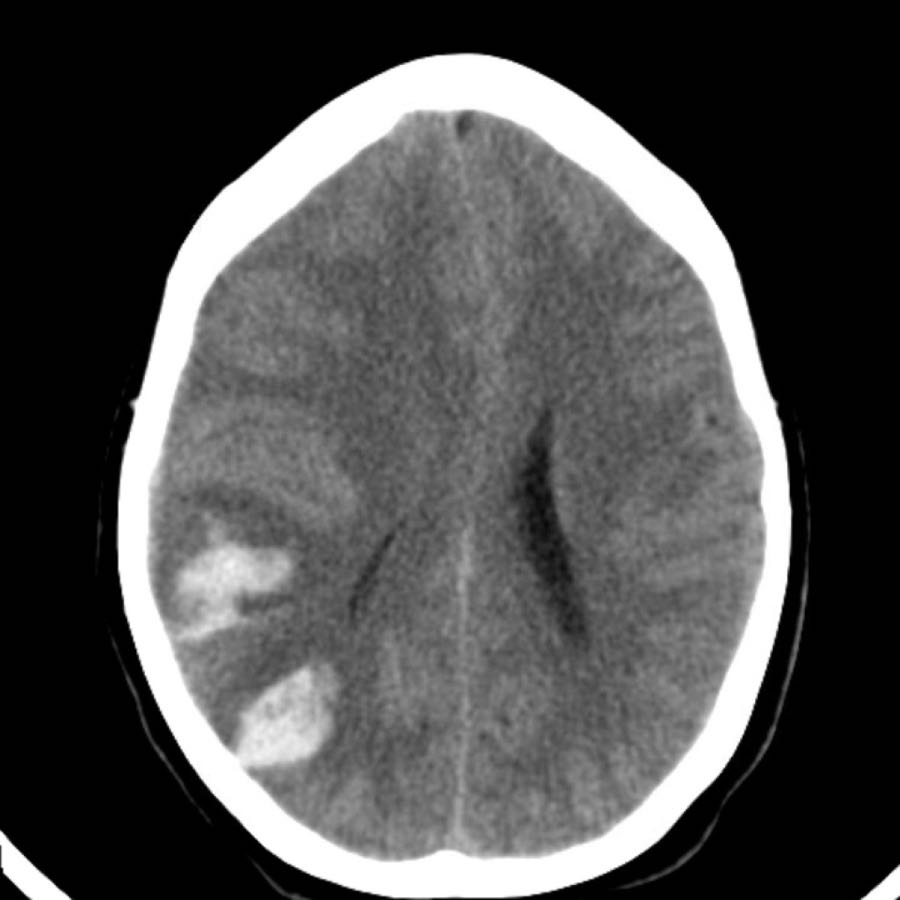

Dưới đây là một số ví dụ về xuất huyết thùy não.

Chảy máu vào hệ thống não thất trong xuất huyết thùy não ít phổ biến hơn so với xuất huyết do tăng huyết áp do vị trí ngoại vi hơn.

Chỉ khi tổn thương rất lớn mới có thể gây chảy máu vào hệ thống não thất (hình).

Bệnh nhân này tử vong vào ngày hôm sau.

Không có chẩn đoán xác định nào được đưa ra, nhưng được cho là trường hợp CAA.